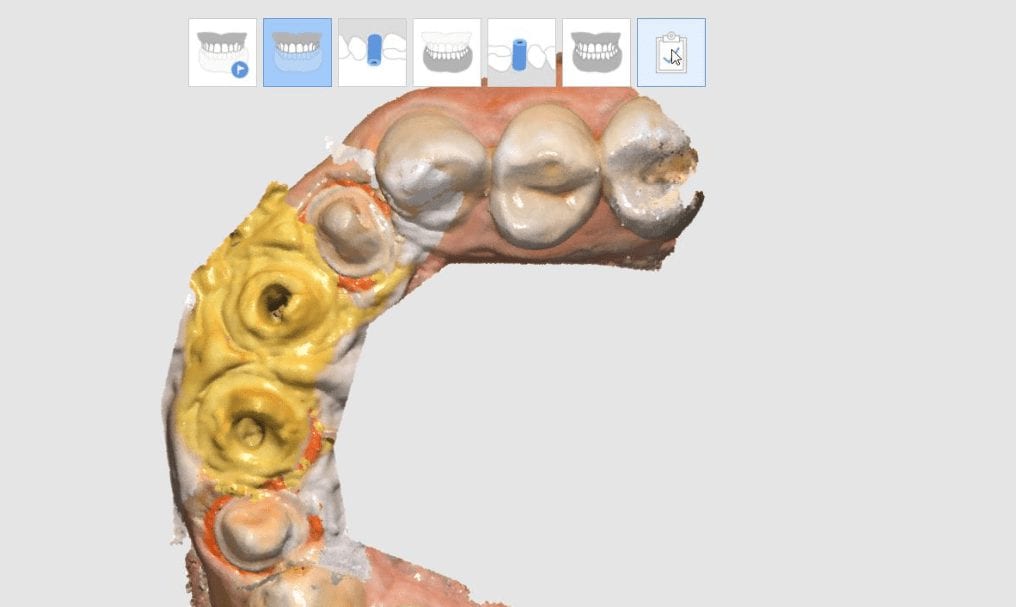

Bridge Replacement with the Medit i500 Using Copy Mode of the Pre-op, White Light for Red Tissue, Blue Light for Tooth Structure, and Segmented Model Building

February 4, 2019This failing three unit fixed partial denture was replaced with the Medit i500 and the CAD-Ray Design Software. While the patient was getting numb, a physical quadrant impression was made […]